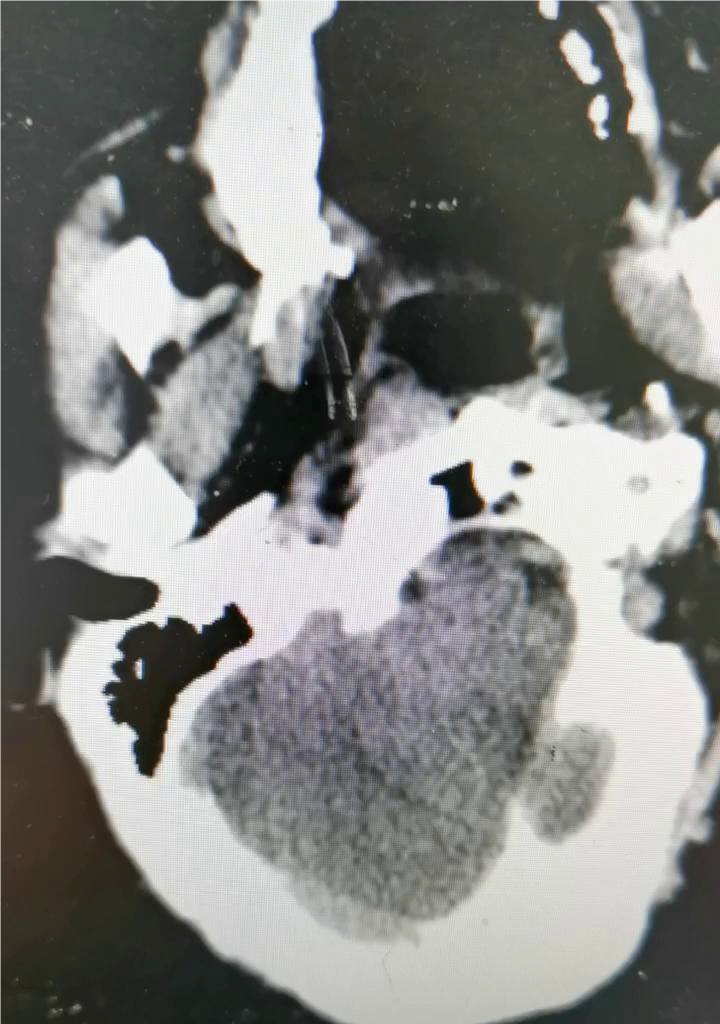

术前右侧椎动脉造影

术前左侧椎动脉造影

左侧颈总动脉造影

右侧颈总动脉造影

左侧椎动脉起始部成形

确认血栓远近端

血管再通后造影

血管再通及左椎支架植入

左椎支架植入后造影